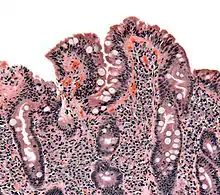

| The ileocecal valve prevents reflux of bacteria from the colon into the small bowel. Resection of the valve can lead to bacterial overgrowth. | |

Finally, abnormal connections between the bacteria-rich colon and the small bowel can increase the bacterial load in the small bowel. Patients with Crohn's disease or other diseases of the ileum may require surgery that removes the ileocecal valve connecting the small and large bowel; this leads to an increased reflux of bacteria into the small bowel. After bariatric surgery for obesity, connections between the stomach and the ileum can be formed, which may increase bacterial load in the small bowel.[26]